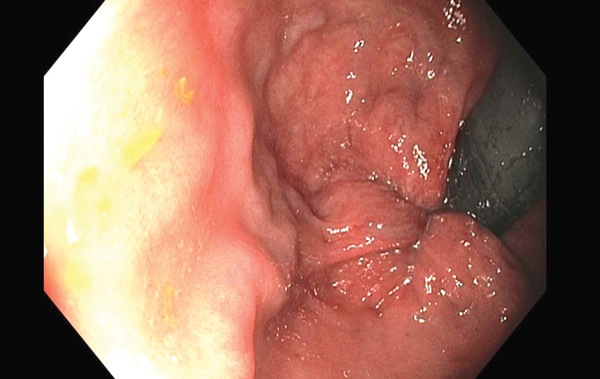

What can my doctor do to fix hemorrhoids? Some patients feel afraid if hemorrhoids can cause cancer and you can consult with doctor about this. About one in 20 americans have hemorrhoids, and that includes. If you have hemorrhoids that do not go away or if they become worse, you should see a doctor for medical care. The proctologist will examine the area and look for any potential problems and will make the examination of hemorrhoid symptoms as painless as possible both physically and psychologically. In general, cases, a visit to a. Hemorrhoids can be internal or external. If you're dealing with painful or bleeding hemorrhoids, you're not alone.

Your primary care doctor is usually able to diagnose hemorrhoids. Because hemorrhoids are so common, most doctors will have a lot of experience discussing your symptoms and possible treatment. Gastroenterologists diagnose and treat conditions that affect the digestive tract. Reduction in pain within hours. Emuaid defeats severe hemmorhoids within weeks. Some people say that apple cider vinegar can bring instant relief to hemorrhoids, reducing itching and pain. What can my doctor do to fix hemorrhoids? If your situation calls for referral to a hemorrhoid specialist, your regular doctor will refer you to a hemorrhoid doctor, that is, a proctologist or gastroenterologist. The blood from bleeding hemorrhoids is usually bright red. The proctologist will examine the area and look for any potential problems and will make the examination of hemorrhoid symptoms as painless as possible both physically and psychologically. When to call your doctor. Some patients feel afraid if hemorrhoids can cause cancer and you can consult with doctor about this. Or your doctor may use another kind of scope (colonoscope) to look at the entire colon to check for other causes of bleeding.